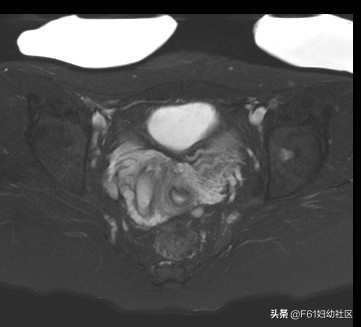

上图为阴道上端横断位图,可见阴道内见一肌性分隔把阴道腔分为两个腔。

1、阴道上端积血及阴道内可见斜隔终止于一侧阴道壁。